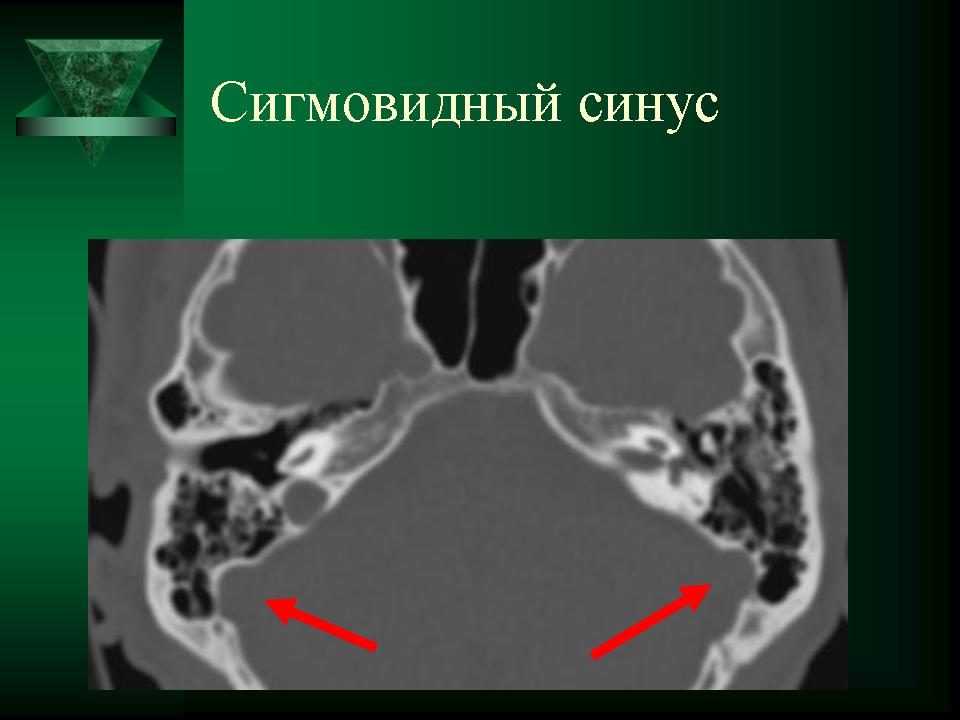

КТ анатомия сосцевидного отростка: особенности и показания